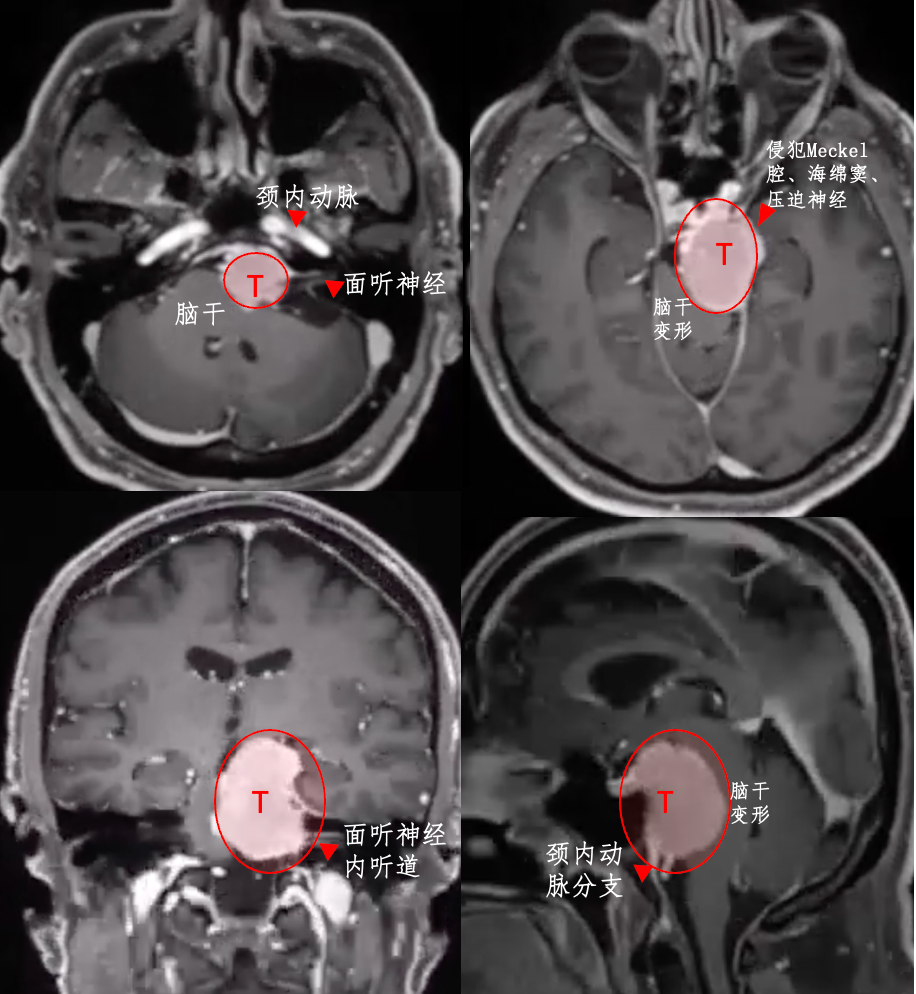

一例岩斜区脑膜瘤,患者出现左侧脸部剧痛、吞咽困难等严重症状。2014年,刚查出时,考虑到这是个良性肿瘤,且手术治疗有风险,选择了保守观察。然而,6年时间,肿瘤持续增长,压迫脑干,症状不断恶化。

CT检查发现肿瘤出现钙化,意味着肿瘤质地硬,切除困难,在切除时容易损伤周围血管和神经。

福教授采用开颅手术,在切除肿瘤过程中,使用CUSA刀对肿瘤逐渐减瘤。术后MRI显示肿瘤几乎完全切除,脑干受压解除。